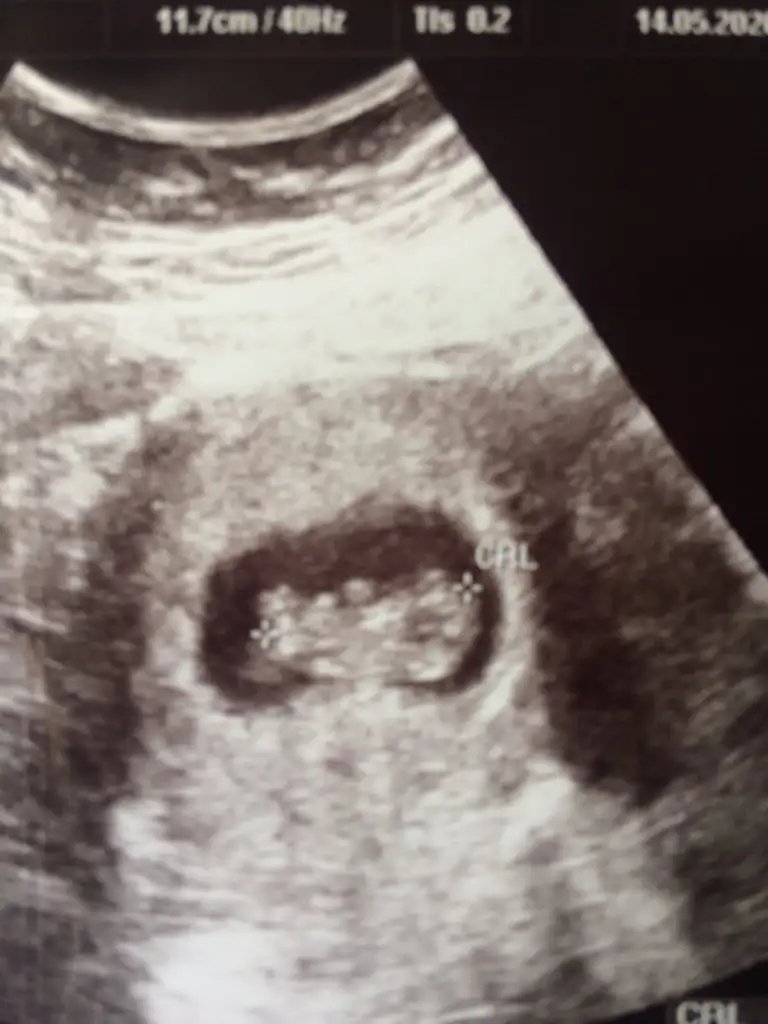

Yerim seni yerrr erkek gbigeldi bana eger dogruysa kizlarin dedigi yere bakdimm

Ben bunu kıza benzettim canım ama bir dahaki randevunda daha net olur